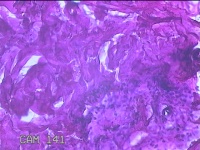

臀部肿物

性别

女

年龄

32岁

临床诊断

脂溢性角化病;皮肤感染

一般病史

颈部臀部丘疹数年。

标本名称

大体所见

灰白粉红色带皮肤样肿物1.8x0.5x0.2cm一个,表面糜烂。